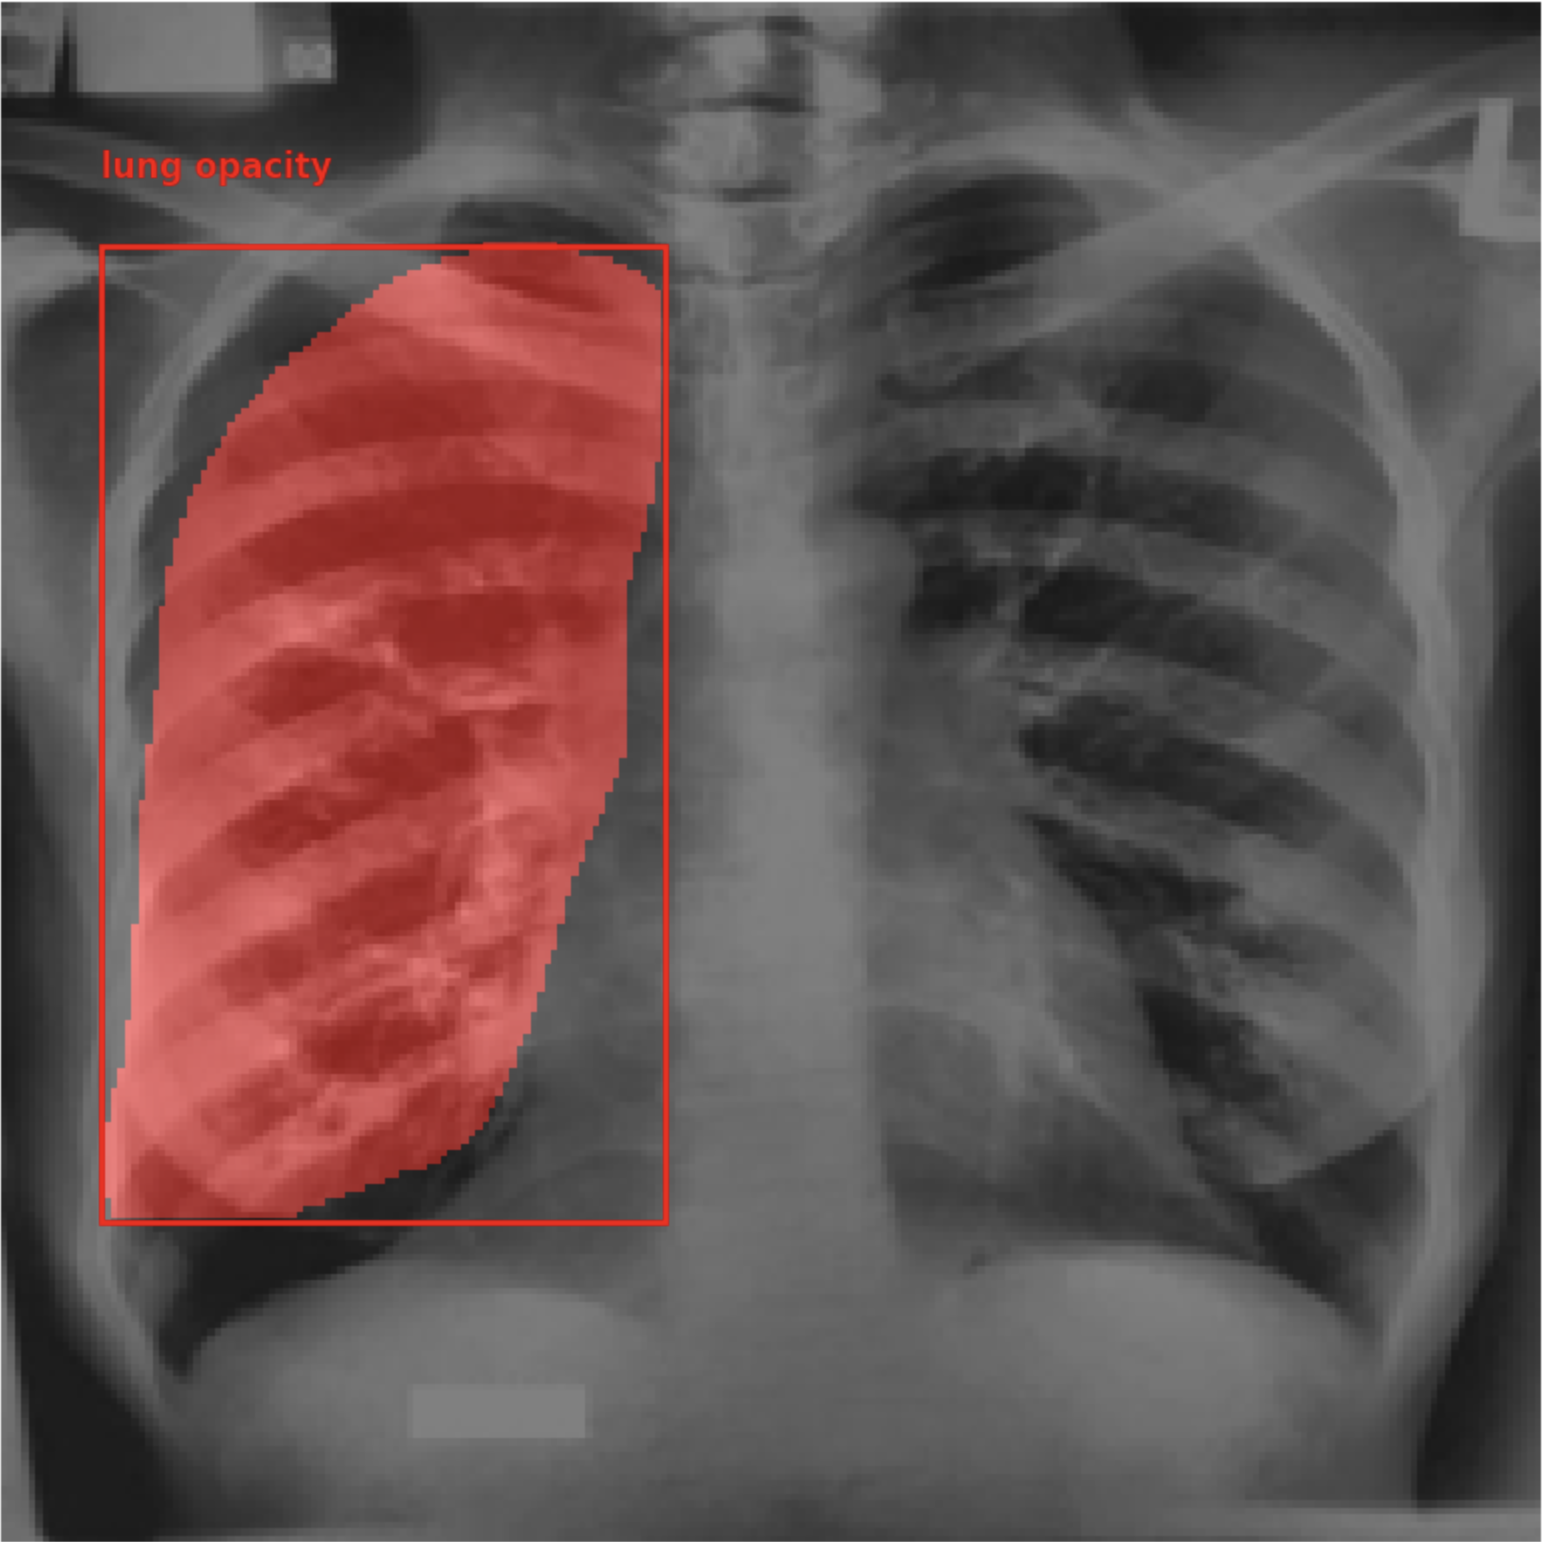

Figure 1: Images from the training dataset. (a) shows an image with active TB, (b) shows a TB negative image, (c) shows an image with latent TB, (d) shows an image with bounding box, and (e) shows an image with segmentation masks.

Figure 4: (a) shows the bounding boxes predicted by PaliGemma-CXR and (b) shows the ground truth bounding boxes, (c) shows the ground truth segmentation mask and (d) shows the segmentation mask generated by PaliGemma-CXR.

Figure 4, shows the segmentation masks predicted by PaliGemma-CXR. It successfully segments predicts segmentation masks with a high IoU with the ground truth segmentation mask.